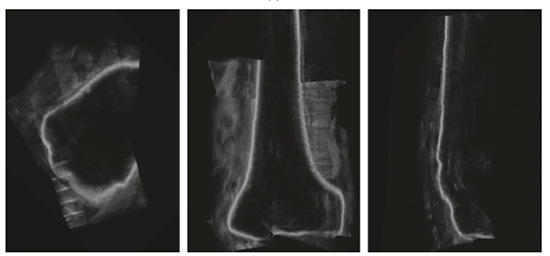

Las estructuras óseas aparecen en las imágenes de ultrasonido como regiones con bordes brillantes seguidas de una región obscura, resultado de la sombra acústica generada por el hueso como se observa en la figura 1. La alta intensidad del reflejo acústico provocado por el hueso se observa en las imágenes como una línea de espesor entre 2 y 4mm. Característica que debe ser tomada en cuenta para que las dimensiones de la superficie extraída correspondan con el tamaño original del hueso del paciente. Jain et al., [4] demuestran que la cortical del hueso se encuentra en el máximo de intensidad del gradiente generado por la respuesta del hueso al ultrasonido. El resultado activa un detector que realza la línea media para que tenga una representación más precisa de la cortical ósea en imágenes de ultrasonido que los métodos basados en detección de bordes.

Figura 1. Muestra una imagen de ultrasonido de la meseta tibial. En esta se pueden apreciar artefactos del ultrasonido como la sombra acústica, las reverberaciones y la cortical ósea